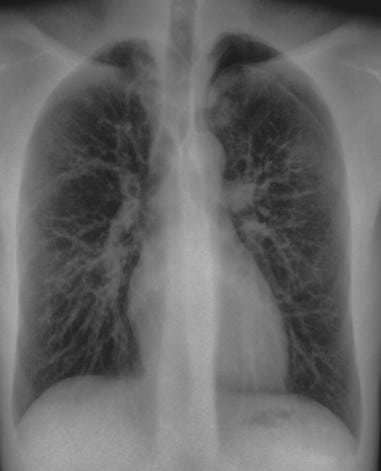

In this case, the conventional DR image shows subtle findings. The spectral soft-tissue image reduces overlying bone, making the pneumothorax more conspicuous. The corresponding bone-selective image highlights a rib fracture, a potential underlying cause of the pneumothorax.

Pneumothorax Evaluation

Soft-tissue images reduce rib overlap and may improve visualization of pneumothorax in trauma patients.

Rib and Skeletal Trauma